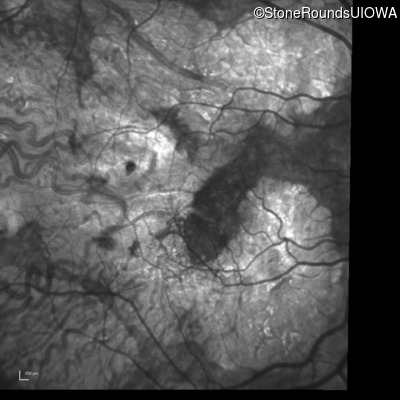

Infrared Fundus Photograph - Right - 20/40 -2

Exemplar

Infrared Fundus Photograph - Left - 20/40 +1